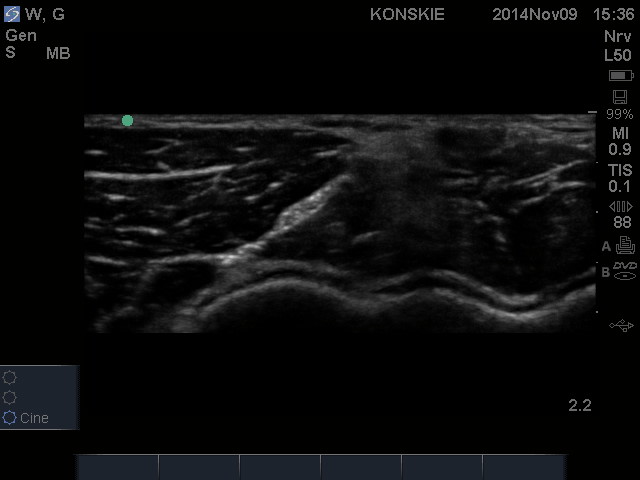

W obrazie ultrasonograficznym w okolicy jednej trzeciej dystalnej ramienia n. promieniowy przybiera kształt trójkątnego hiperechogenicznego tworu, położonego pomiędzy mięśniem trójgłowym a głową boczną mięśnia dwugłowego. W okolicy dołu łokciowego n. promieniowy początkowo biegnie w powięzi pomiędzy mięsniem ramienno-promieniowym a mięśniem ramiennym gdzie mniej więcej na wysokosci 2-3 cm powyżej bruzdy łokciowej, ukazuje się jako podłużna, wrzecionowata, hiperechogeniczna struktura, wciśnięta pomiędzy dwa wyżej wymienione mięśnie.

Sonoanatomia nerwu promieniowego na wysokości szczeliny stawu łokociowego. RN – nerw promieniowy (radial nerve)